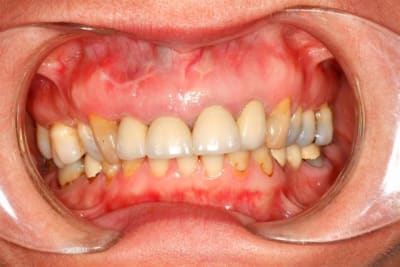

Entre 2 implants, je travaille sur ce cas.

Des idées ?

Suite :

Paro stable, furcation normale.

Patiente ne désire pas de chirurgie style Lefort (pour le gummy smile), ni d'ortho.

J'ai placé 2 implants (14 et 35)

Le bridge 34-X-36 était brisé et troué (pour une endo), et la patiente désirait des dents unitaire.

J'ai placé des provisoires de 13 à 23 suite à

l'élongation de 13 à 23 et apectomie 12.